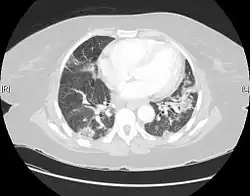

Usual interstitial pneumonia seen on CT scan. Honeycomb fibrosis is seen at the bases of both lungs.

UIP may be diagnosed by a radiologist using computed tomography (CT) scan of the chest, or by a pathologist using tissue obtained by a lung biopsy.

Radiologically, the main feature required for a confident diagnosis of UIP is honeycomb change in the periphery and the lower portions (bases) of the lungs.[3]